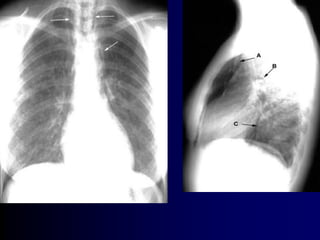

1-Year Therapy With MFNS Did Not Induce

Nasal Atrophy in Patients With PAR1,a

Nasal Biopsies

Before MFNS Treatment After 12 Months of Treatment With

MFNS 200 µg/d

Disruption of epithelium

Eosinophil infiltration

Epithelium intact

No eosinophil infiltration

aThe clinicalrelevance ofthese data in the treatmentofallergic rhinitis is notknown.

MFNS = mometasone furoate nasalspray;PAR= perennialallergic rhinitis.

1. Minshall E et al. Otolaryngol Head Neck Surg. 1998;118:648–654.